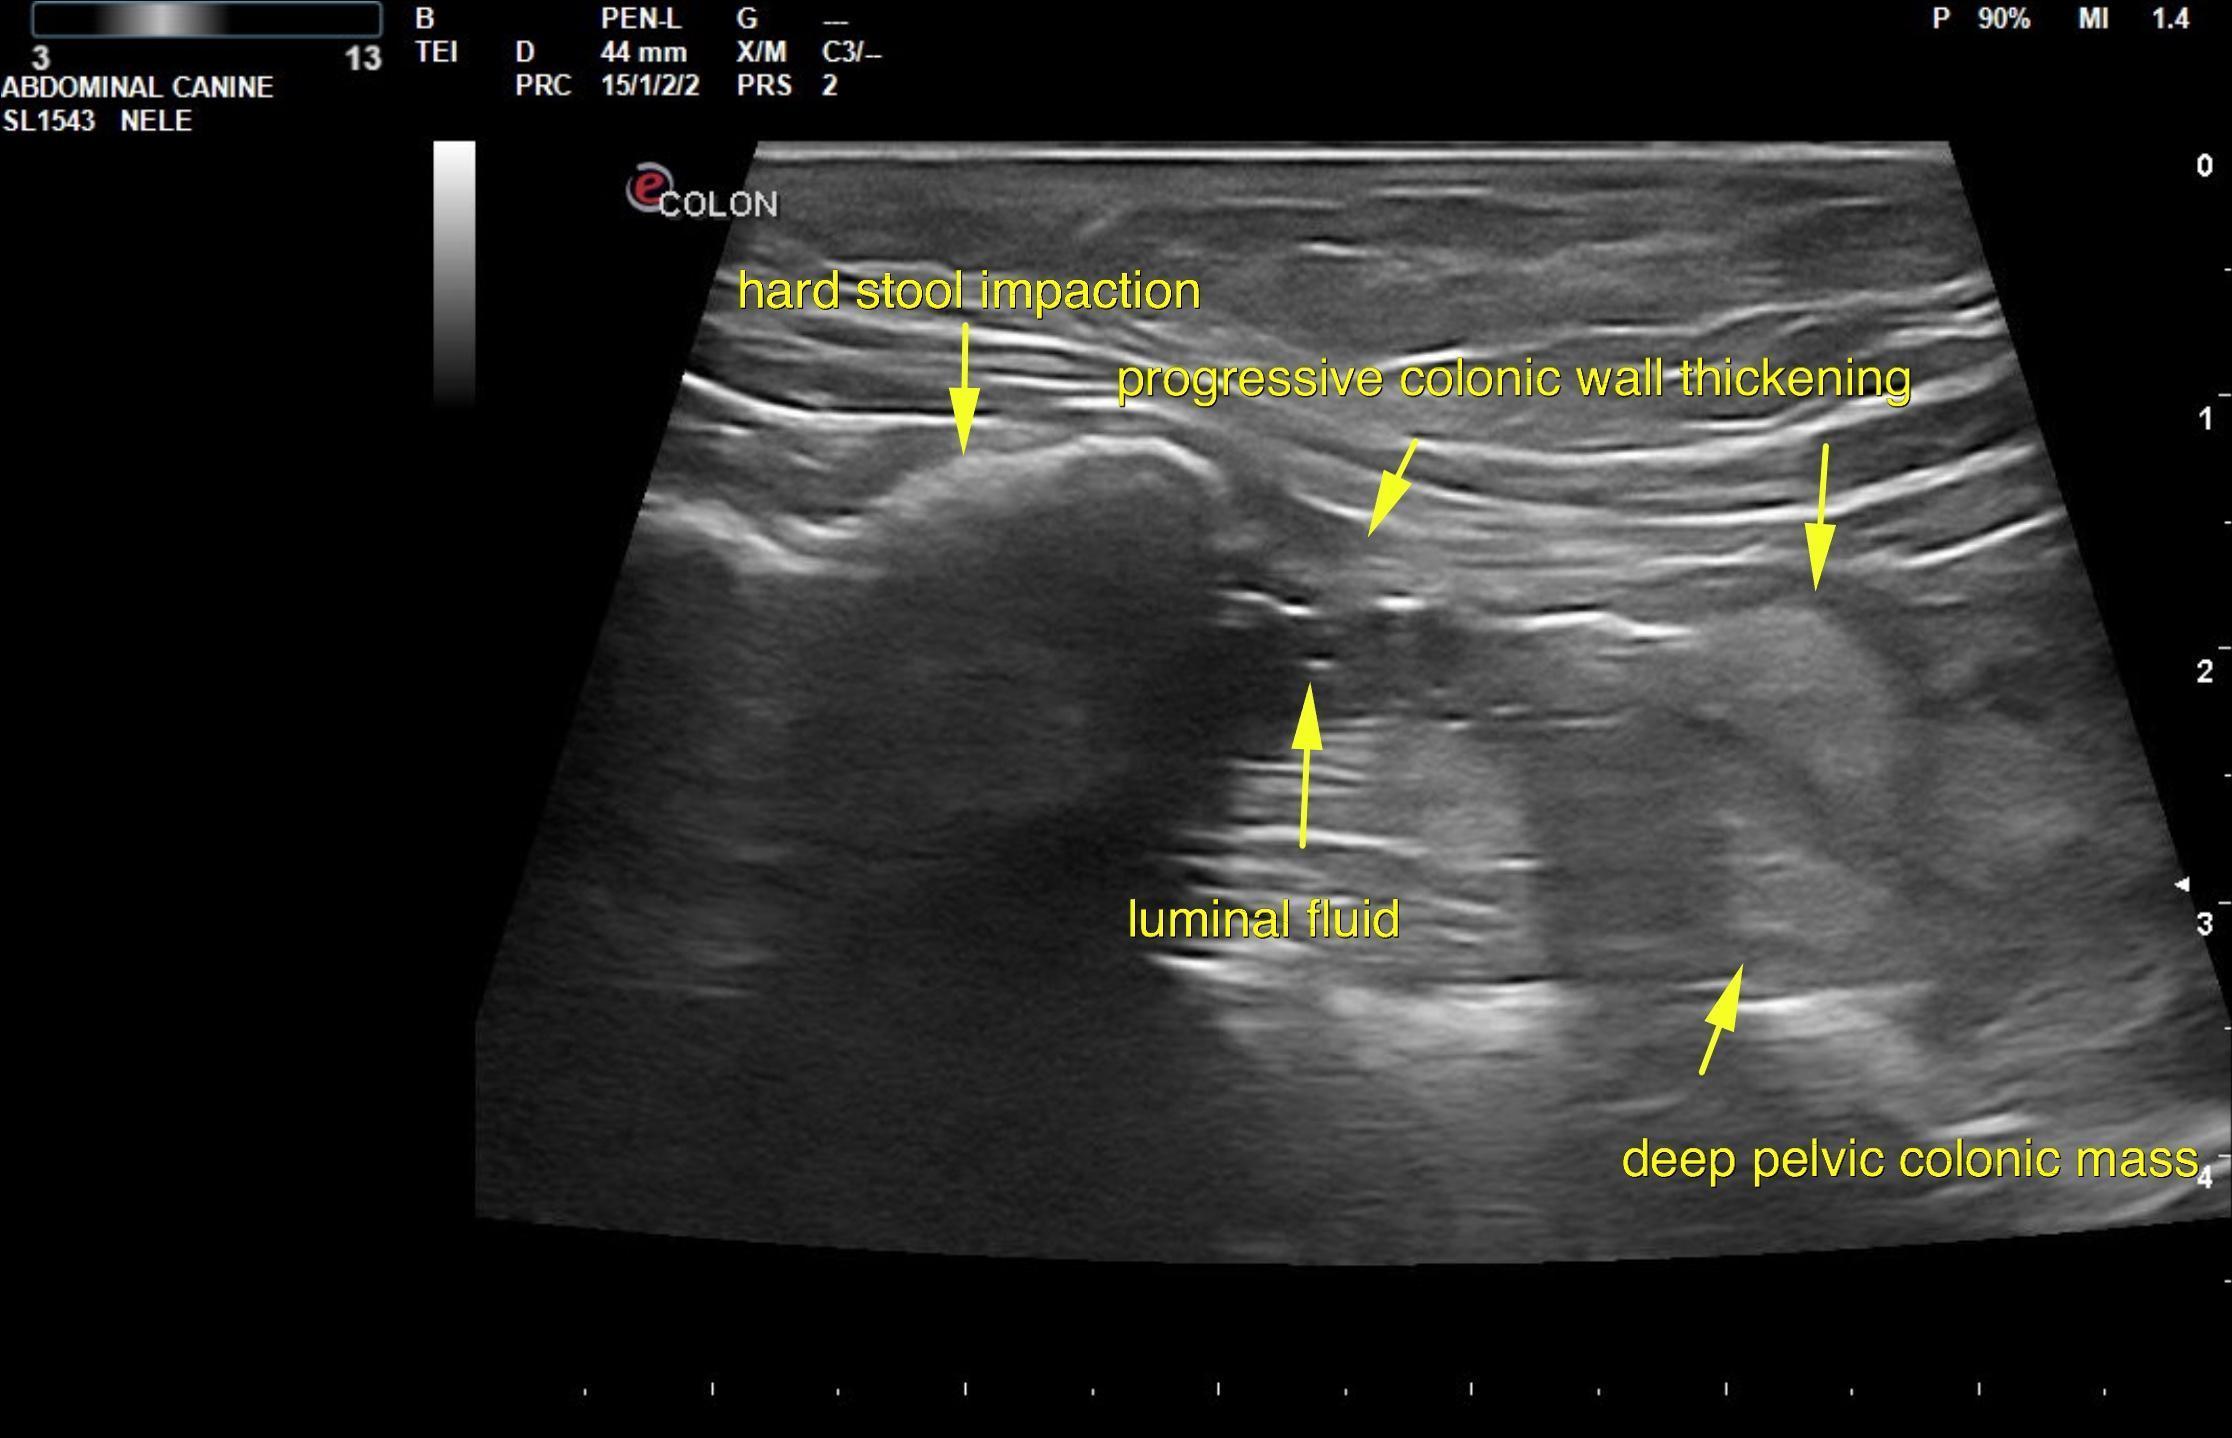

The colon in this patient revealed an approximately 2.0 x 4.0 cm concentric mass with an obstructive pattern. Hypoechoic, ill defined colonic wall was noted. Stool was obstipated from the level of the deep pelvis proximally to the ileocecal junction. The colonic mass appears to be in the distal colon in the pelvic inlet. The mass extended into the colorectal region.

From the perineal approach the colonic mass appears to be reach the colorectum. It does not appear overtly resectable without splitting the pelvis. However, the distal portion of the colonic mass appears to be involved in the colorectum itself. Surgical consultation could be considered. There was no overt evidence of metastatic disease noted. Three view chest radiographs would be warranted. This is likely carcinoma with a minor potential for colonic lymphoma or very mild potential for granulomatous disease. FNA could be attempted if the sonographer is able to find an adequate window for sampling